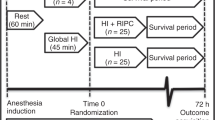

Study design

The study was a randomized placebo-controlled study. Two animals from the same litter and of same sex were included at a time. Prior to CA induction, one animal was randomized to either epinephrine (0.01 mg/kg, equating a volume of 0.1 ml/kg) or placebo (0.1 ml/kg 0.9% saline), and the other animal received the treatment different from the randomized littermate. All investigators were blinded to the allocated treatment during the entire study. The corresponding author was in charge of the study medications; each day, the syringes were filled with an equal volume of epinephrine or placebo. An independent person, not participating in the experiments, labeled the syringes with “Heads” or “Tails”, and logged the details in a document inaccessible to the researchers. We used the online randomization tool “Just flip a coin.”20 After randomization, the volume of the syringes was adjusted to the weight of the animal.

One of the 28 animals was not randomized due to unsuccessful arterial access. ROSC occurred before treatment intervention in 2 of the remaining 27 animals (one from each group); these animals were euthanized after ROSC. All 27 animals were included in an intention to treat analysis (Supplementary S4). The two animals that achieved ROSC before treatment were excluded from the final analysis as described in ref. 22. The following results are based on per protocol analysis of 25 animals: epinephrine (n = 13) vs placebo (n = 12). We found no difference in results analyzed according to intention to treat vs per protocol. A flow chart is presented in Supplementary S5.